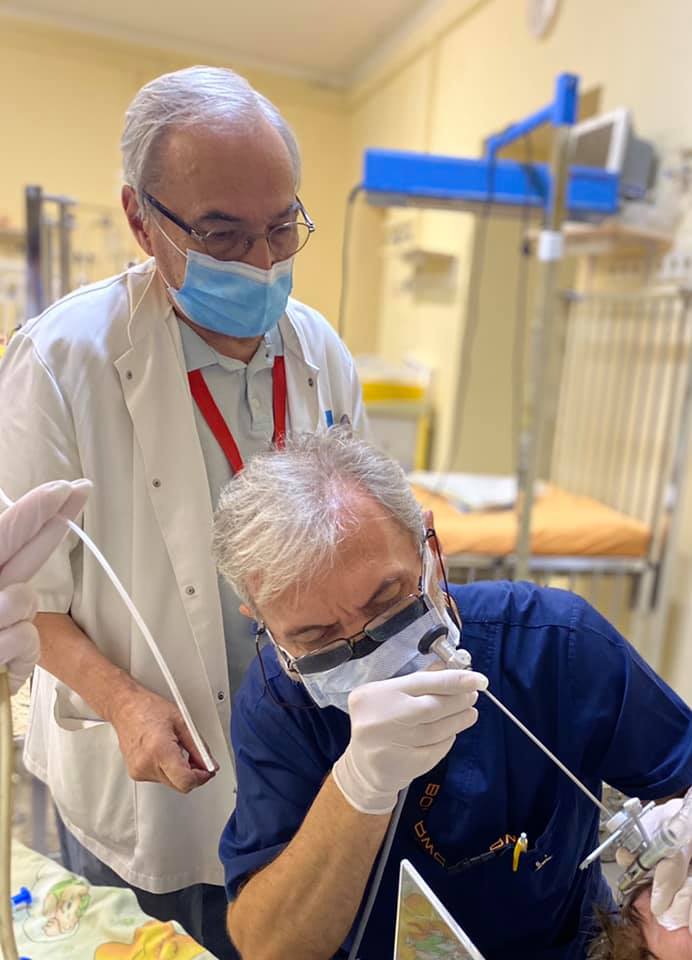

Хірурги виконали складну операцію місячній дівчинці зі Стрия

У Львівській дитячій обласній лікарні «Охматдит» торакальні хірурги виконали складну операцію місячній дівчинці зі Стрия, в якої була вроджена діафрагмальна грижа. Вони забрали шлунок, селезінку і кишківник з грудної клітки та помістили у черевну порожнину.

“У нашої дівчинки тонкий кишківник і частина товстої кишки, шлунок і селезінка опинилися у грудній клітці, а ліва легеня не мала як розвиватися, вона була недорозвинена. Всі ці органи з черевної порожнини тиснули на цю маленьку легеню, сердечко і здорову легеню, і не давали їм повноцінно працювати. Тут ніякий орган не був на своєму місці! Порушилися відразу і газообмін, і обмін речовин, і гемодинаміка”, – пояснив торакальний хірург, який лікував місячну дитину, Олег Ленів.

Як повідомили в лікарні, порятунок дівчинки відбувався в три кроки. По-перше, лікарі налагодили дихальну функцію. Дитину перевели на спеціальний високочастотний апарат ШВЛ. Він необхідний, щоб не порушувалася робота інших органів. По-друге, власне, відбулася сама операція: була відкрита хірургія, але не через усю грудну клітку і черевну порожнину. Хірурги зробили доступ через маленький розріз у 3 см. Третій крок – це виходжування дитини у відділенні реанімації новонароджених.

- Фото: ФБ/ОХМАДИТ

- Фото: ФБ/ОХМАДИТ

- Фото: ФБ/ОХМАДИТ